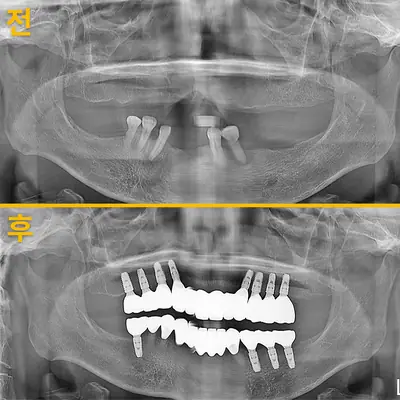

치과 치료를 두려워하는 분들에게 희망적인 사례를 소개합니다. 부산에 거주하던 60대 여성 환자가 치과 공포로 치료를 미루다 치아 상태가 악화되어, 의식하 진정요법을 통해 안전하게 임플란트 치료를 받은 이야기입니다. 환자는 병원 트라우마와 주사 공포, 치과 공포증이 있었지만, 전문의의 세심한 관리와 진정요법 덕분에 큰 불안 없이 치료를 마칠 수 있었어요. 치료 과정은 발치, 임플란트 수술, 인상 채득, 보철물 장착까지 단계별로 진행되었으며, 치료 후 자연스럽고 안정된 치아와 잇몸 라인을 확인할 수 있었습니다. 이 사례는 치과 공포증이 심한 분들도 적절한 진정요법과 신뢰를 바탕으로 치료받을 수 있음을 보여줍니다. 먼 거리에서도 찾아오는 환자들이 많은 이유는 바로 이런 진심 어린 진료와 결과 덕분이죠. 치과 치료에 대한 두려움이 있다면, 전문가와 상담하여 적합한 방법을 찾는 것이 중요합니다.